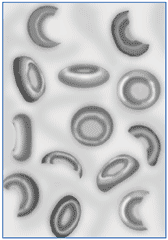

Гемолитическая анемия

Гемолити́ческая анеми́я (лат. anaemia haemolytica от др.-греч. αἷμα «кровь» + λύσις «разрушение, растворение» + анемия) — групповое название редких заболеваний, общим признаком которых является усиленное разрушение эритроцитов, обусловливающее, с одной стороны, анемию и повышенное образование продуктов распада эритроцитов, с другой стороны — реактивно усиленный эритропоэз.